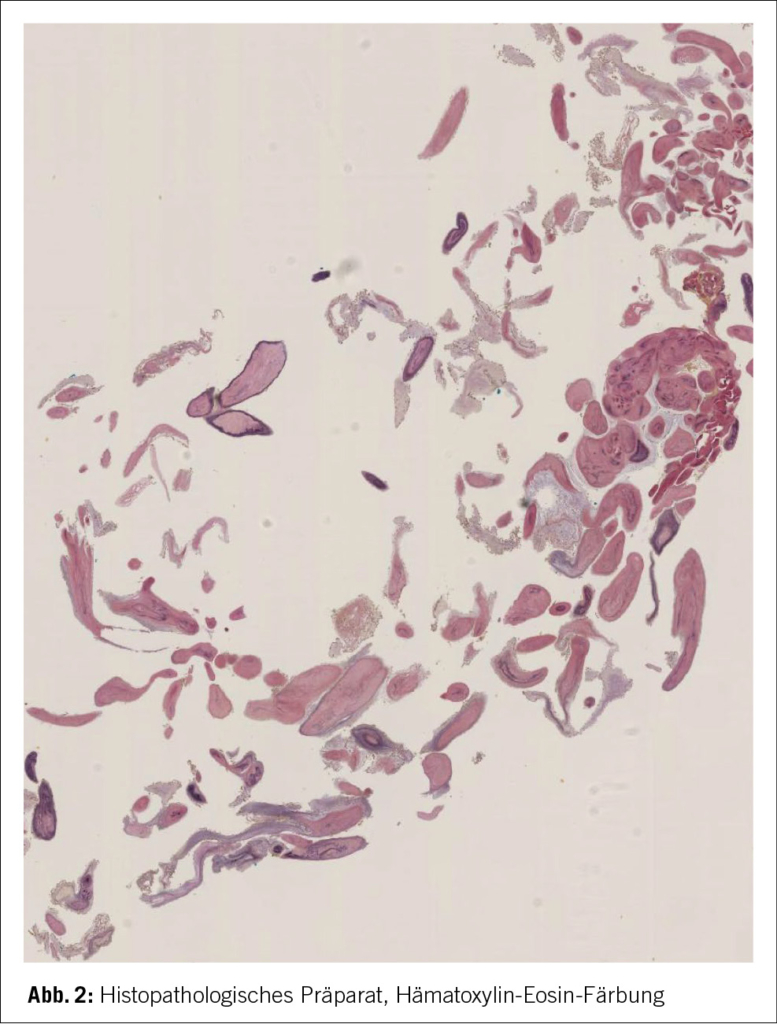

In der Bildgebung mittels Schädel CT-Angiografie, bestätigte sich eine akute Ischämie rechtshemisphärisch im Mediastromgebiet bei M1-Verschluss der MCA rechts mit relativ grosser Penumbra und bereits Infarktdemarkierung in der Insula, Capsula externa, Putamen, periventrikulärem Marklager bis hin zur Cauda nuclei caudati, reichend (Bild 1).

Die typischen neurologischen Ausfälle, mit welchen sich die Patientin initial auf dem Notfall vorstellte, führten zu einer gezielten Bildgebung mittels Schädel CT-Angiographie, wo der Hirninfarkt im rechten Mediastromgebiet, dargestellt werden konnte. Die initialen Abklärungen mittels TTE, Carotis-Sonographie und Herzrhythmusüberwachung, lieferten zunächst keine Ätiologie. Es wurde der Entscheid zur mechanischen Thrombendarteriektomie getroffen, wobei sich letztendlich erst im Thrombusaspirat histopathologisch ein papilläres Fibroelastom, als primäre kardiale Emboliequelle des Schlaganfalls, darstellen liess und die Stroke-Ursache somit geklärt werden konnte.